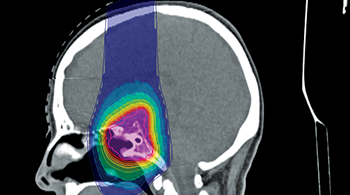

All Dosimetry Neurology Oncology Patient QA Segmentation Simulation & Treatment Planning Oncology PLANET® Onco Dosimetry PLANET® Dose Neurology PLANET® Neuro Segmentation IMAgo Segmentation MorphoBOX Simulation & Treatment Planning SIMAgo Simulation & Treatment Planning ISOgray® Simulation & Treatment Planning ISOgray®-Proton Patient QA ThinkQA Suite Patient QA MU2net Patient QA EPIbeam Patient QA EPIgray®